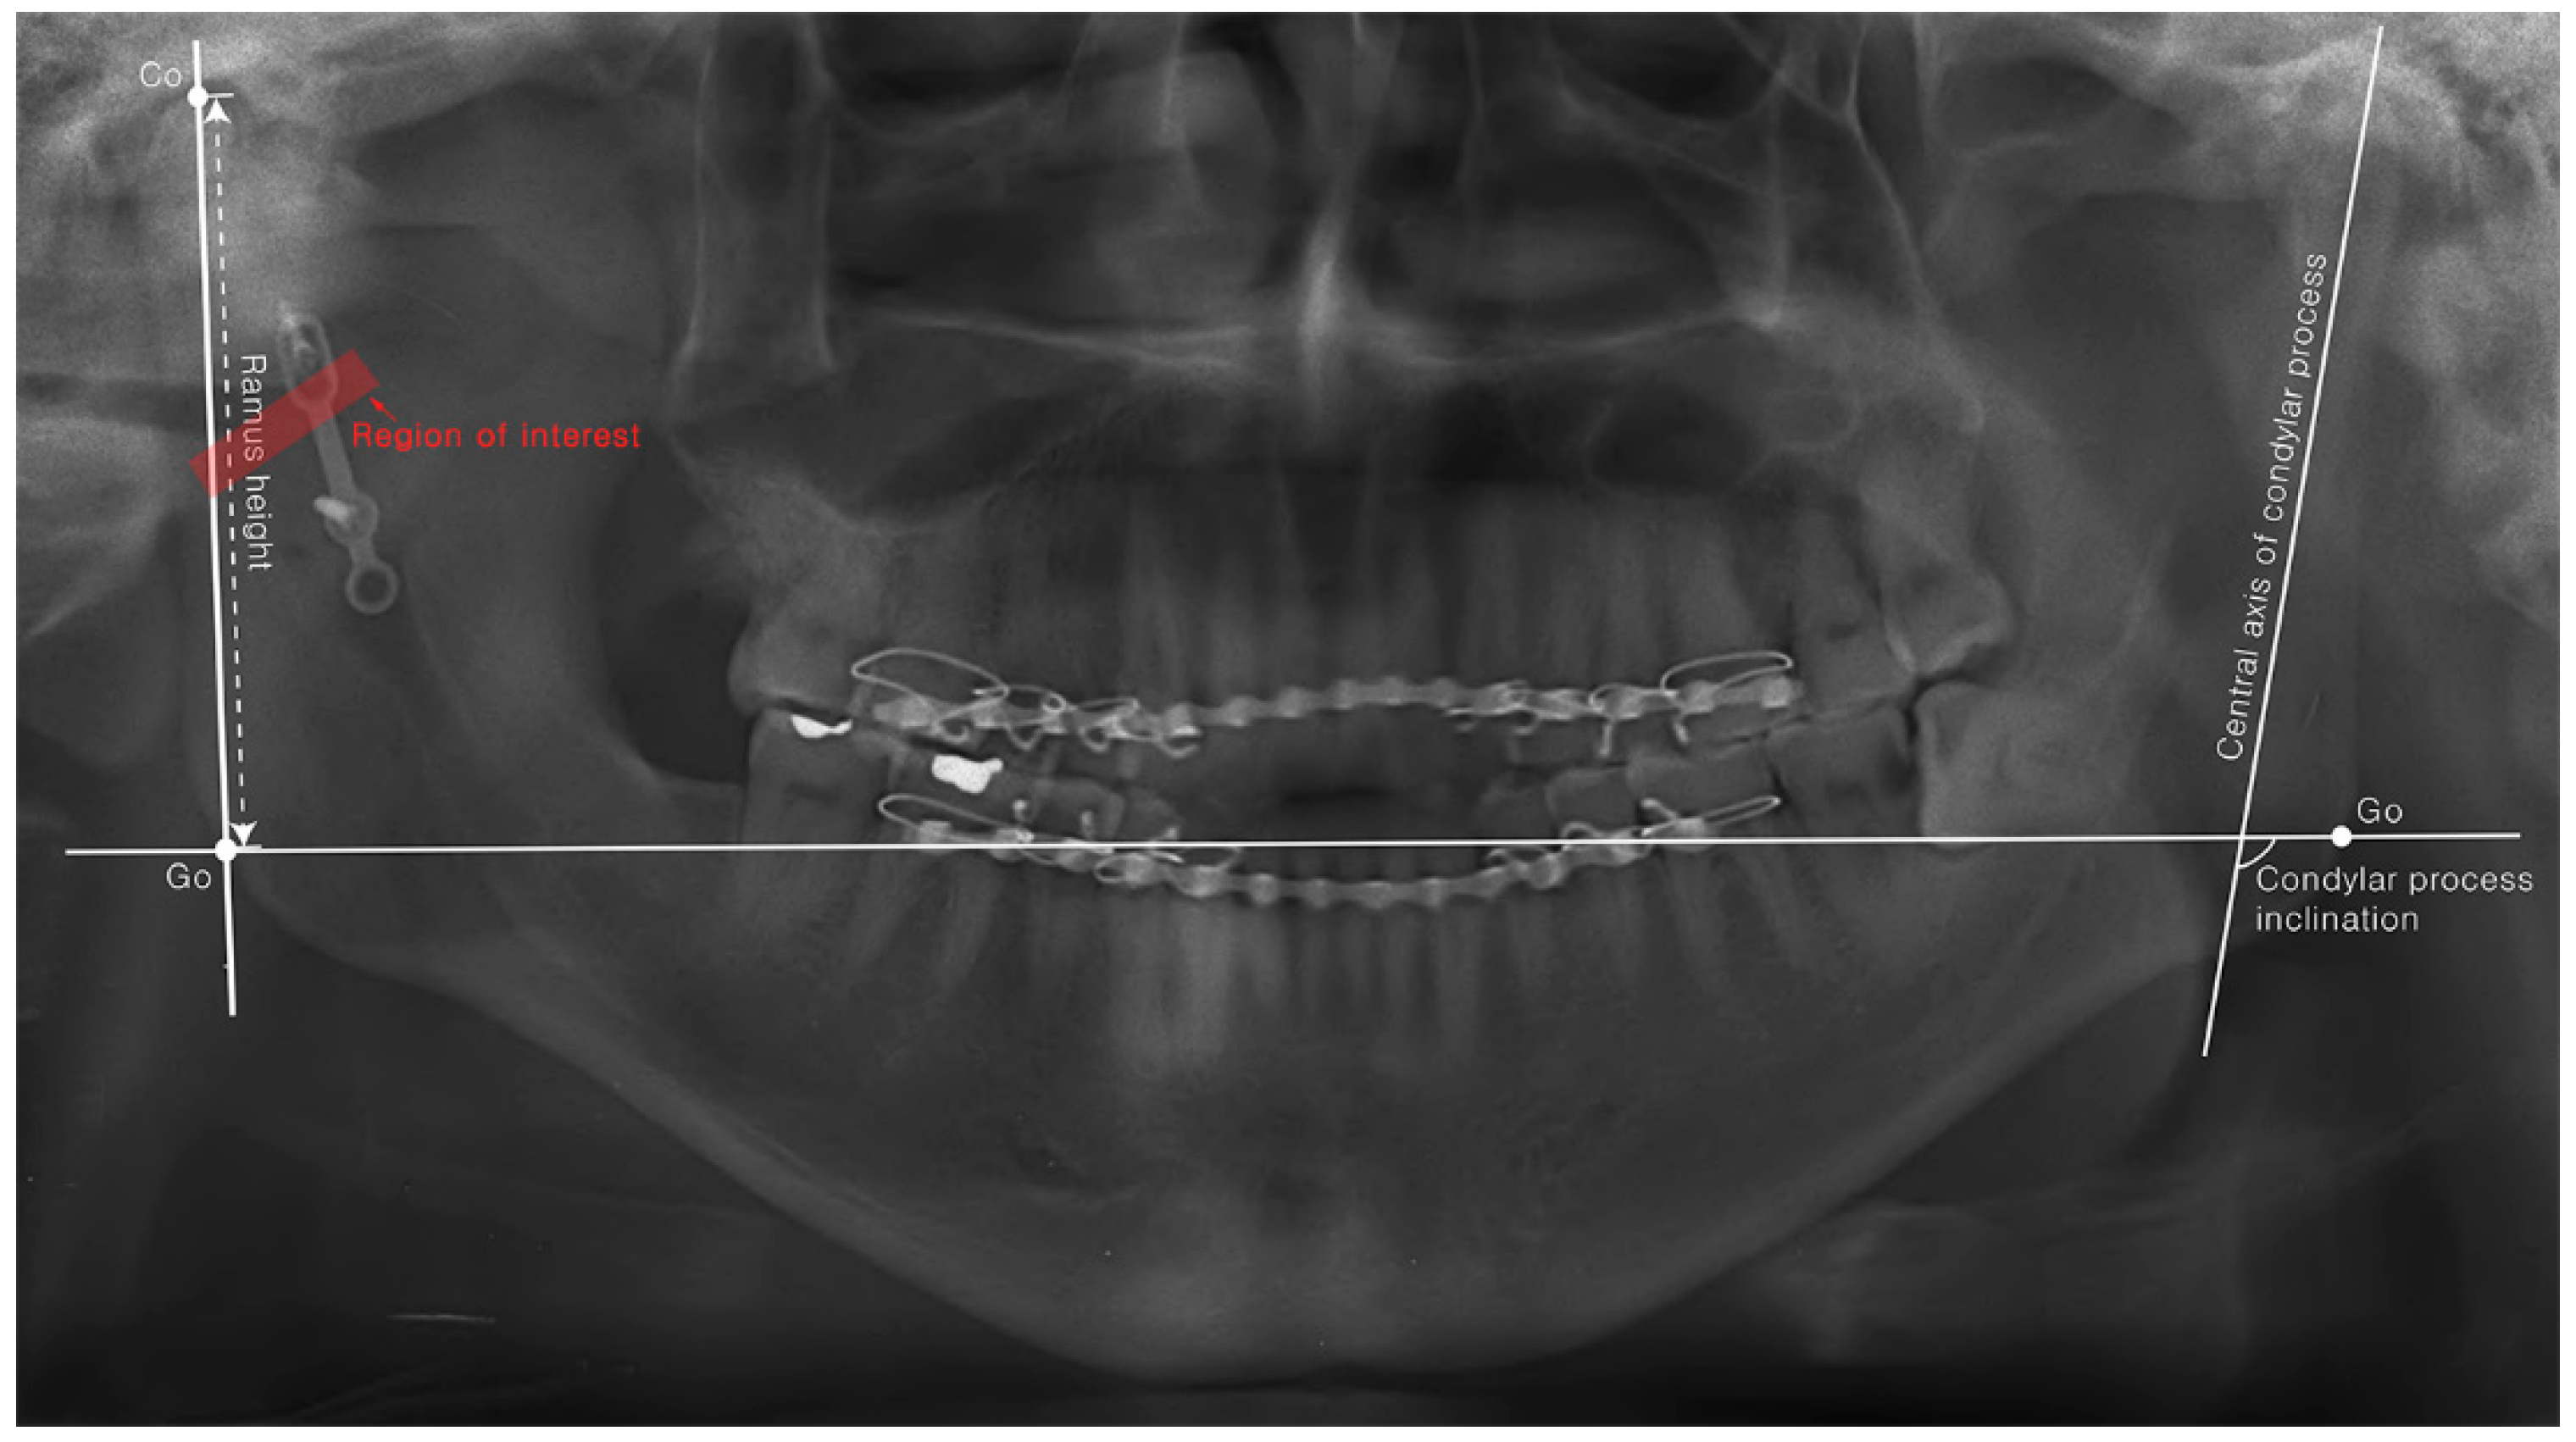

| POD 1D | POD 6M | p-Value | ||

|---|---|---|---|---|

| Differences in ramus height (mm) | Semi-rigid | 4.91 ± 3.79 | 5.50 ± 4.70 | 0.705 |

| Rigid | 3.99 ± 2.85 | 5.35 ± 3.12 | 0.124 | |

| p-Value | 0.734 | 0.786 | ||

| Differences in condylar process inclination (degree) | Semi-rigid | 6.77 ± 5.06 | 6.76 ± 8.36 | 0.723 |

| Rigid | 8.73 ± 10.61 | 12.30 ± 13.07 | 0.246 | |

| p-Value | 1.000 | 0.708 | ||

| Radio-density (Mean grayscale value of ROI) | Semi-rigid | 100.5 ± 17.4 | 102.5 ± 18.4 | 0.035 |

| Rigid | 120.7 ± 31.4 | 124.1 ± 28.7 | 0.044 | |

| p-Value | 0.041 | 0.013 | ||